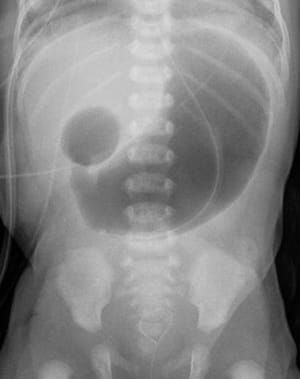

Duodenal Atresia is the congenital anomaly in which there is failure of recanalization of the duodenal canal. The conditions which are associated with it are maternal poly-hydramnions, Downs syndrome and annular pancreas. The child present with abdominal distension, bilious vomiting and dehydration. The abdominal x-ray show the DOUBLE BUBBLE SIGN (pre-stenotic dilation of stomach and proximal duodenum with no distal bowel gas) Management: DUODENODUODENOSTOMY